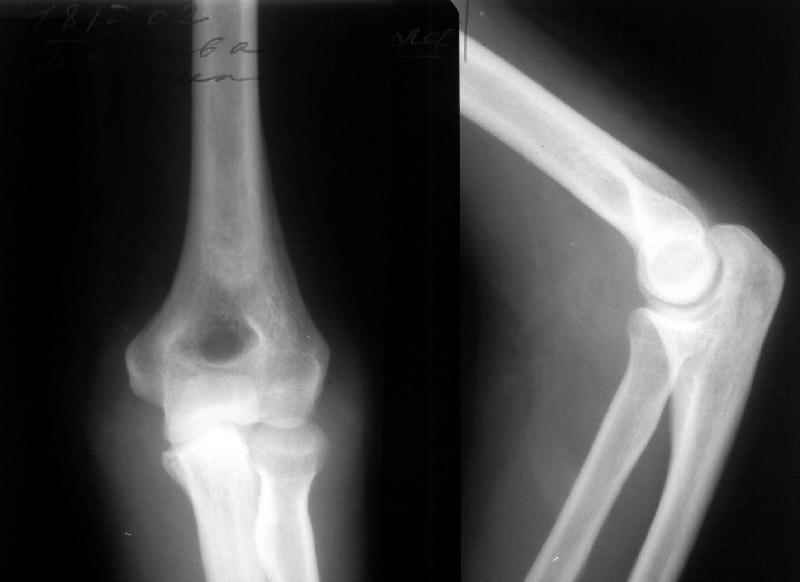

Пациентка 48 лет при падении с 5 этажа получила травму 28.04.02. Среди прочих повреждений был открытый задний вывих предплечья (см. снимок). Он был сразу вправлен, рана 6 см по внутренней поверхности

области локтевого сустава была обработана по месту первичного поступления. К нам поступила 7.05.02. Рана зажила первичным натяжением. Вчера, то есть через три недели после вправления, сняли повязку для разработки движений. Выявлено, что предплечье легко смещается медиально, и вправляется. Движения в локтевом суставе покаплохие. Свежие снимки и в правильном положении, и в подвывихе прилагаются. Вопрос - что делать? Продлить иммобилизацию гипсом? Идти на ревизию и восстановление внутренней боковой связки? Наложить шарнирный аппарат?Заранее спасибо.-- Best regards, Alexander N. Chelnokov